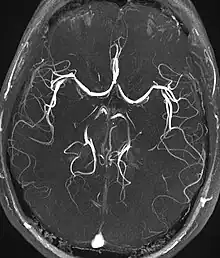

Angiography

Magnetic resonance angiography

Magnetic resonance angiography (MRA) generates pictures of the arteries to evaluate them for stenosis (abnormal narrowing) or aneurysms (vessel wall dilatations, at risk of rupture). MRA is often used to evaluate the arteries of the neck and brain, the thoracic and abdominal aorta, the renal arteries, and the legs (called a "run-off"). A variety of techniques can be used to generate the pictures, such as administration of a paramagnetic contrast agent (gadolinium) or using a technique known as "flow-related enhancement" (e.g., 2D and 3D time-of-flight sequences), where most of the signal on an image is due to blood that recently moved into that plane (see also FLASH MRI).[39]

Techniques involving phase accumulation (known as phase contrast angiography) can also be used to generate flow velocity maps easily and accurately. Magnetic resonance venography (MRV) is a similar procedure that is used to image veins. In this method, the tissue is now excited inferiorly, while the signal is gathered in the plane immediately superior to the excitation plane—thus imaging the venous blood that recently moved from the excited plane.[40]